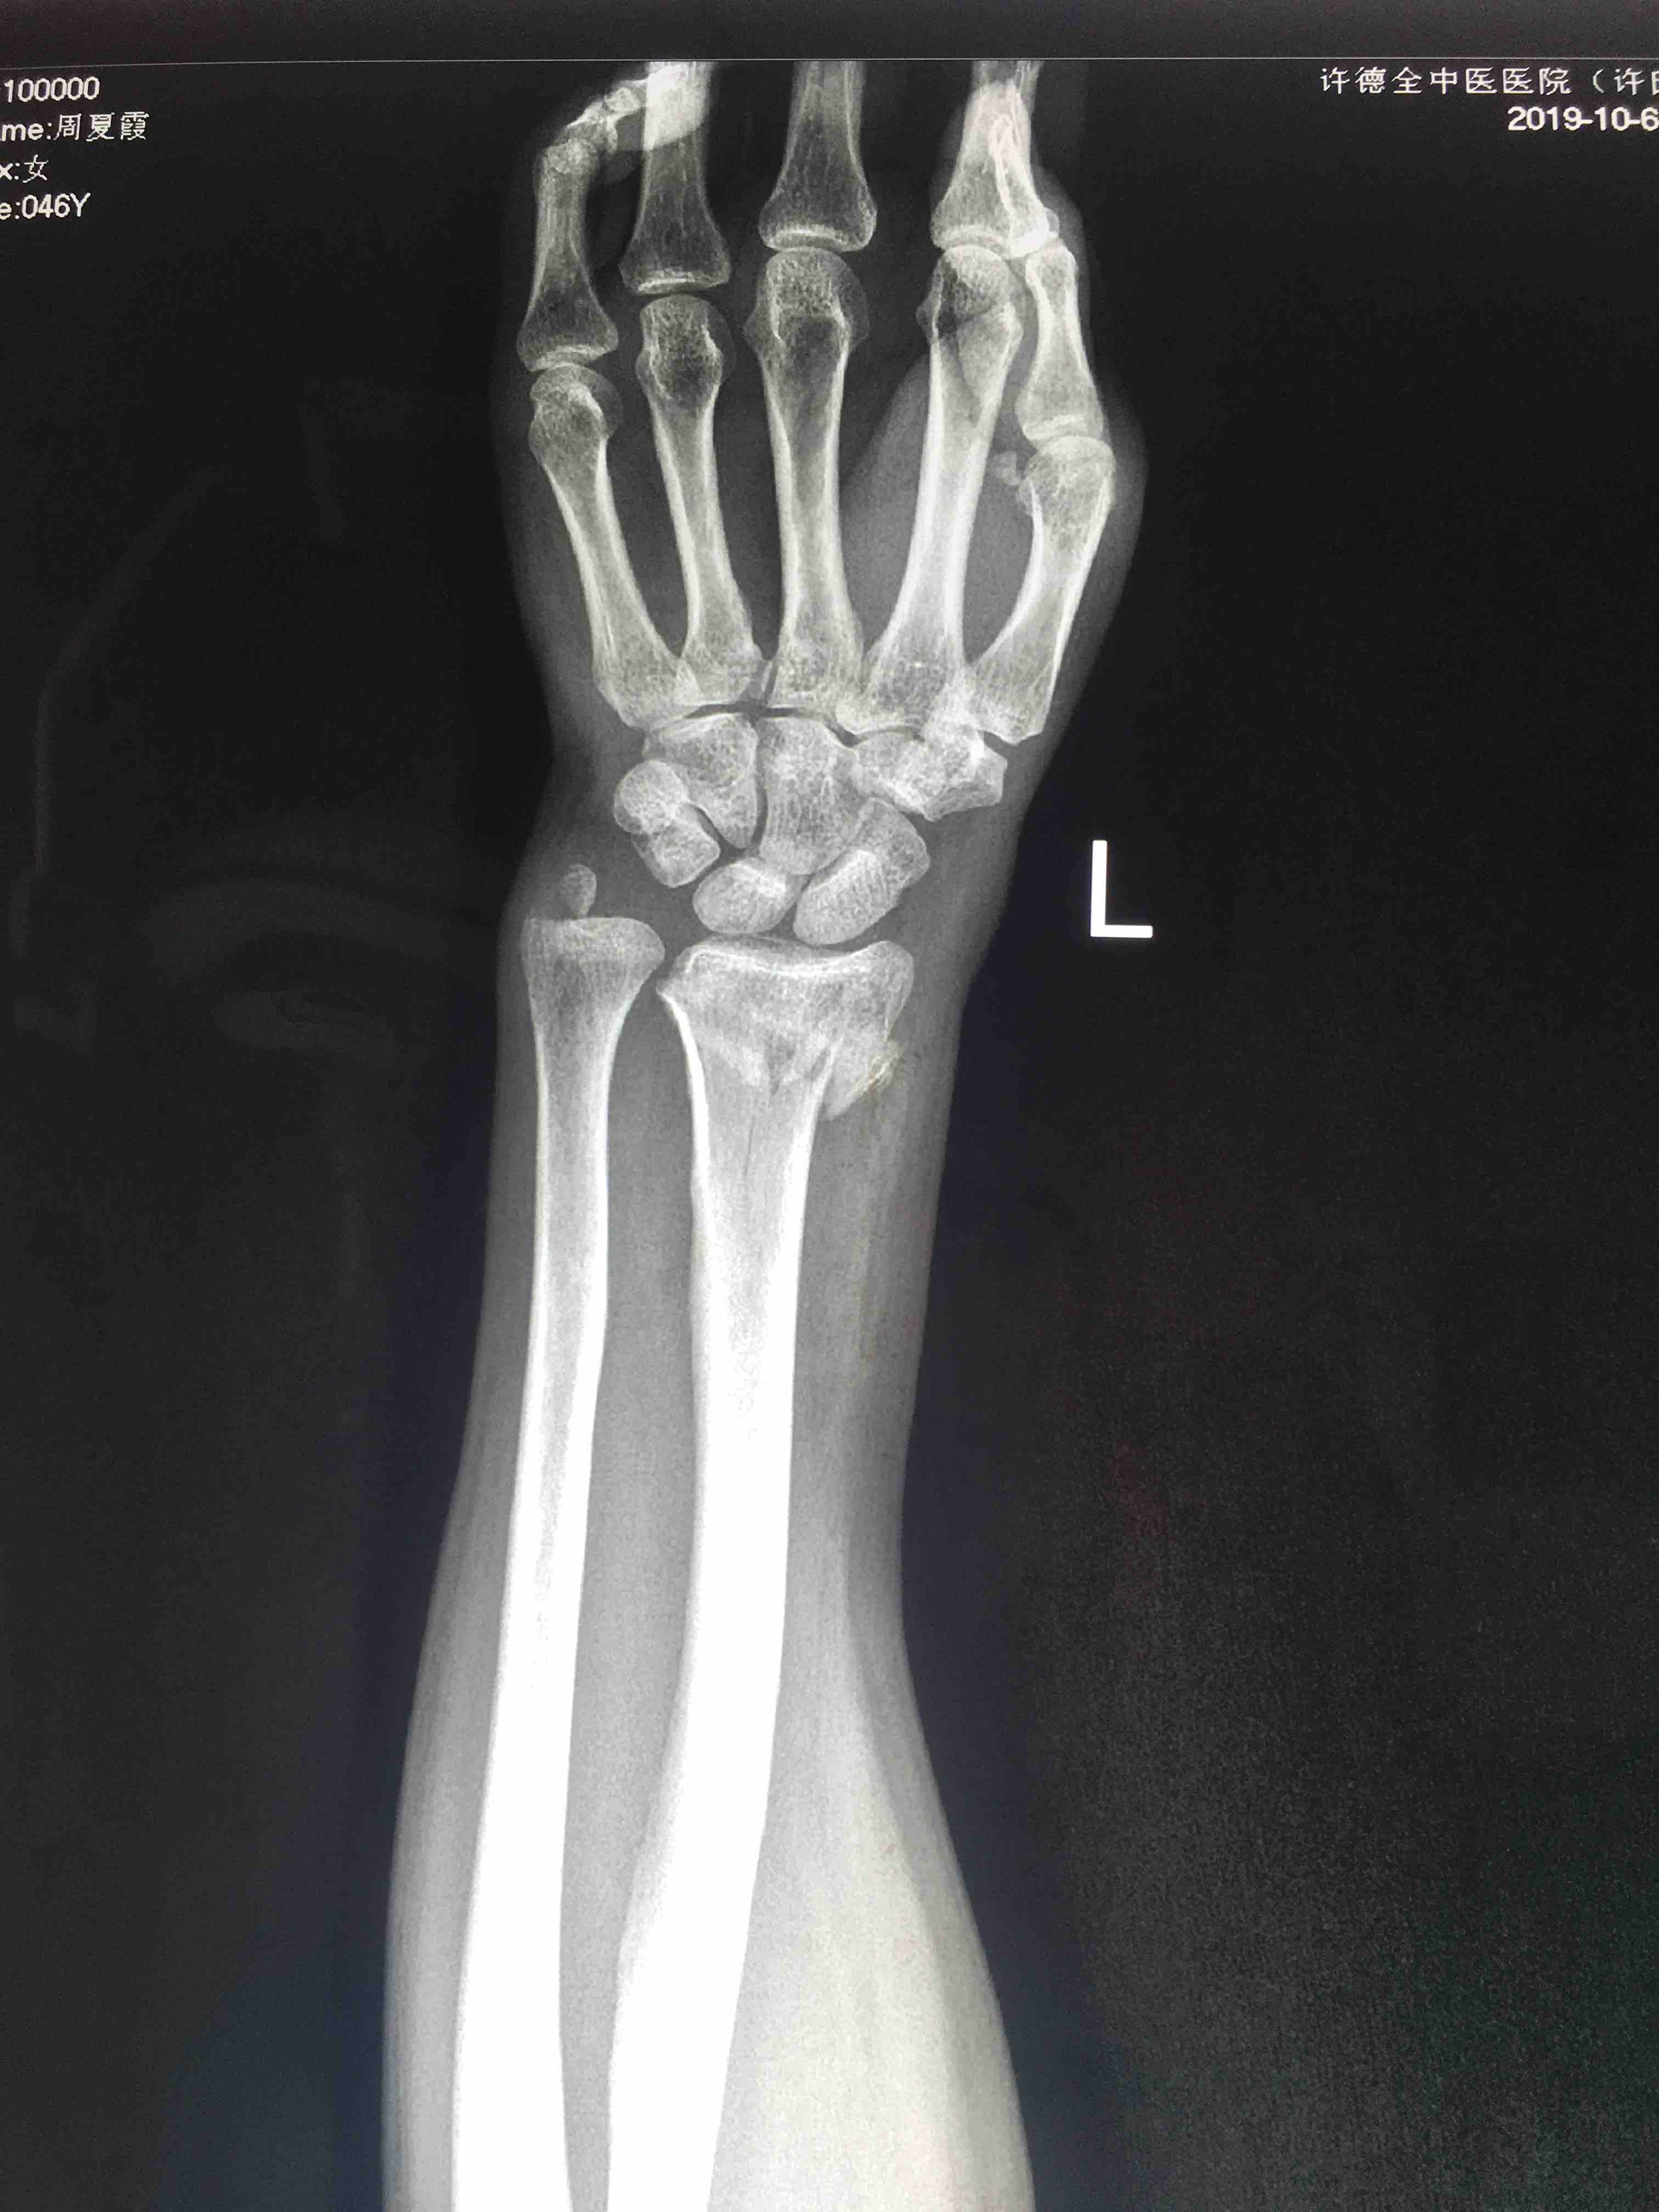

桡骨远端粉碎性骨折(锁定固定)

摔伤后左腕部肿痛,畸形,活动受限1小时入院。既往身体健康,无特殊不良嗜好。

生命体征平稳,心肺复未见异常。左腕部肿胀,畸形,局部皮色皮温正常,压痛及纵叩痛阳性,末梢血运感觉正常。

在臂丛麻醉下行切复内固定术,术后抗炎消肿等处理,